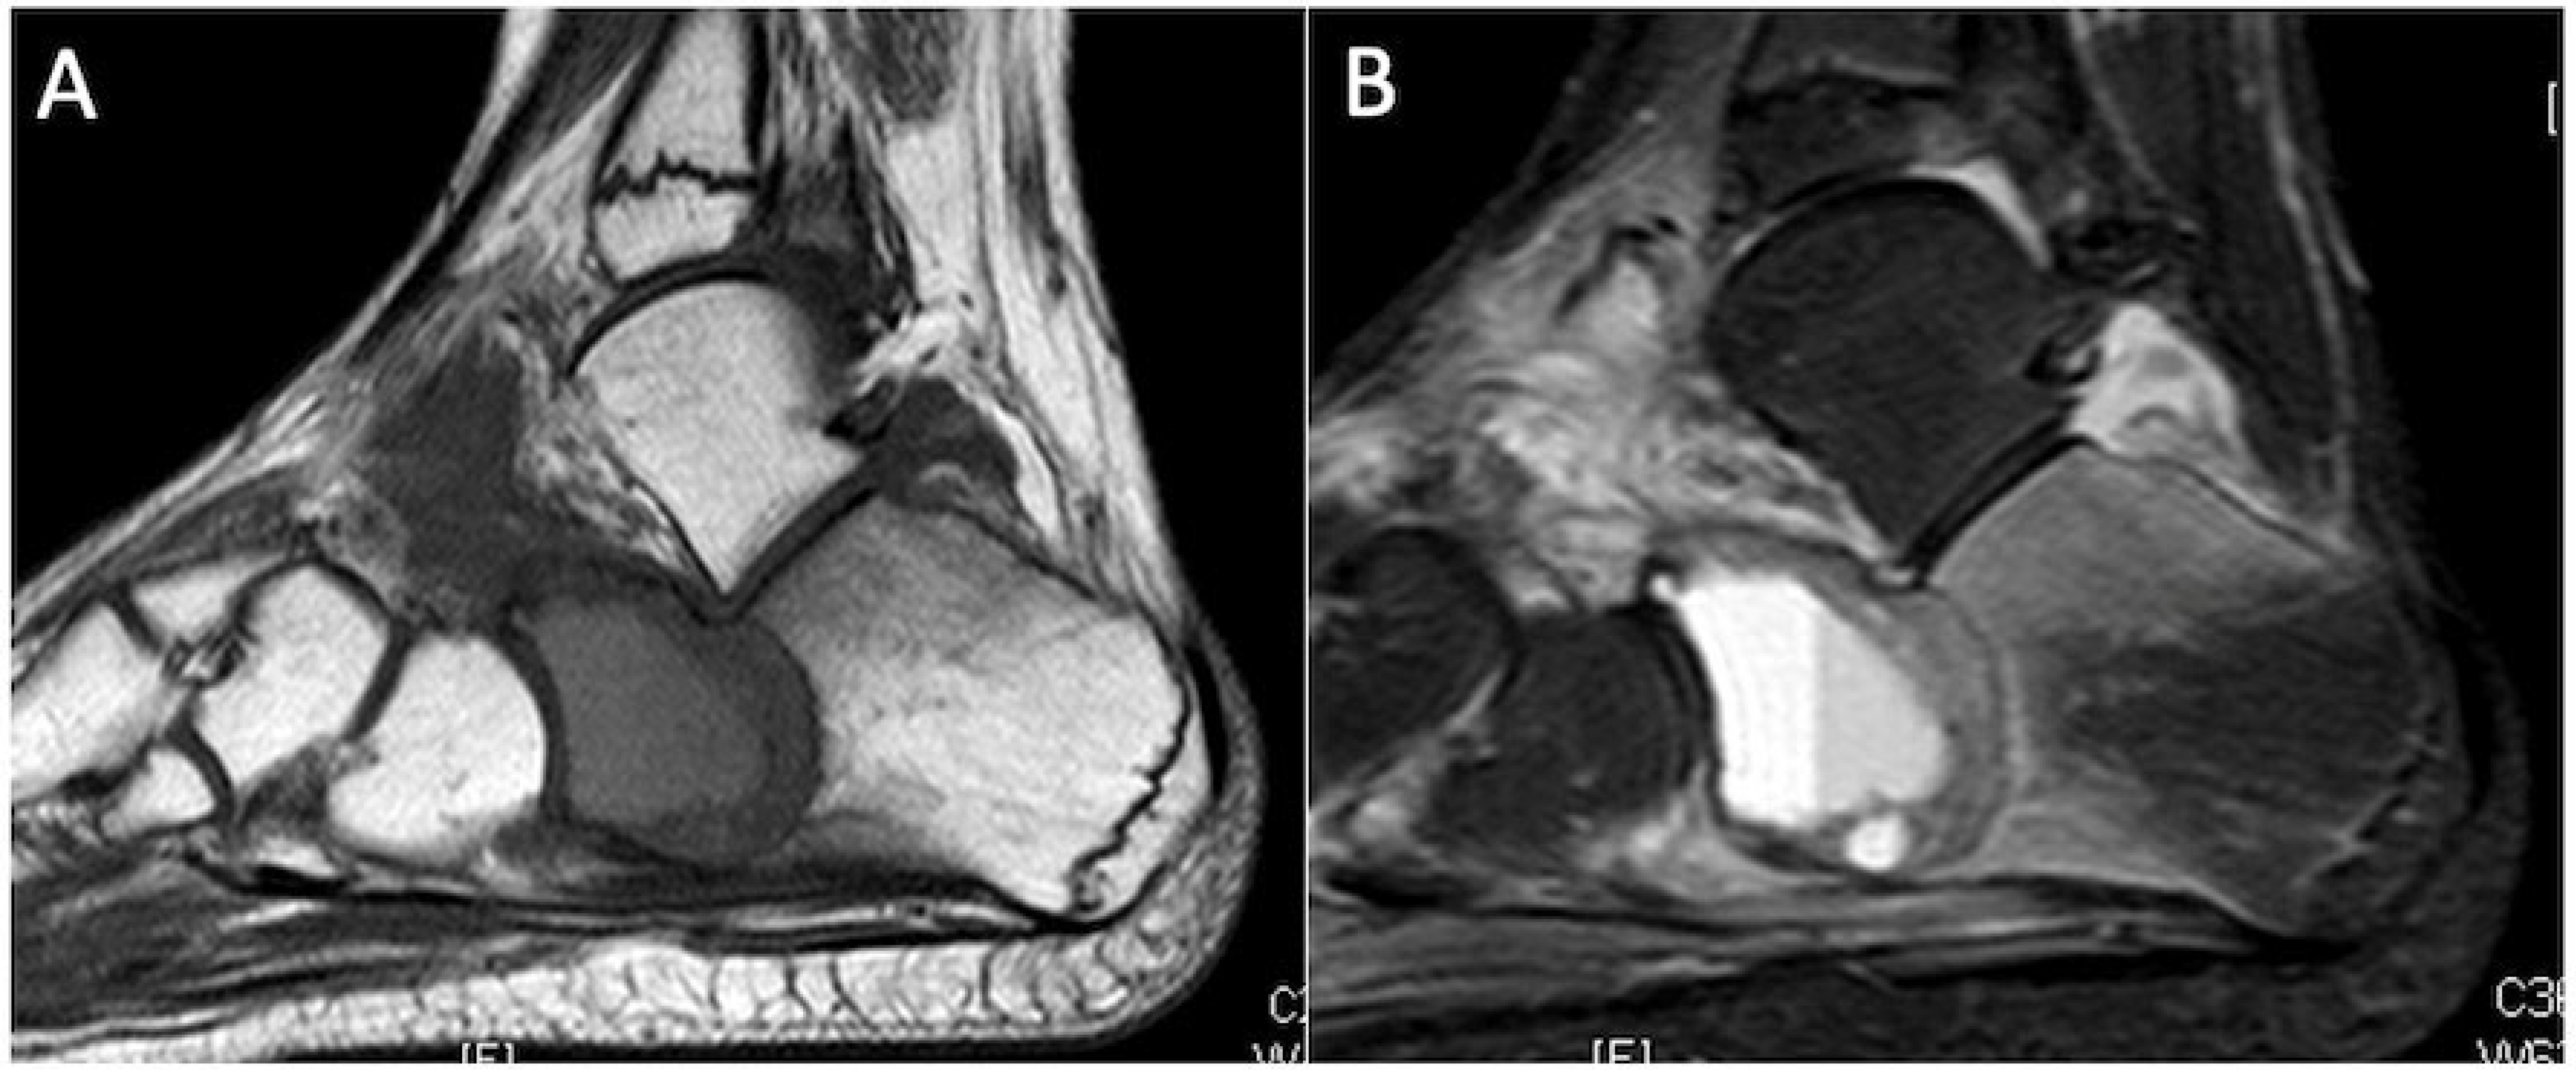

5.1. Chondroblastoma

- Oxtoby, J.; Davies, A. MRI characteristics of chondroblastoma. Clin. Radiol. 1996, 51, 22–26. [Google Scholar] [CrossRef]

- Kaim, A.H.; Hügli, R.; Bonél, H.M.; Jundt, G. Chondroblastoma and clear cell chondrosarcoma: Radiological and MRI characteristics with histopathological correlation. Skelet. Radiol. 2001, 31, 88–95. [Google Scholar] [CrossRef]